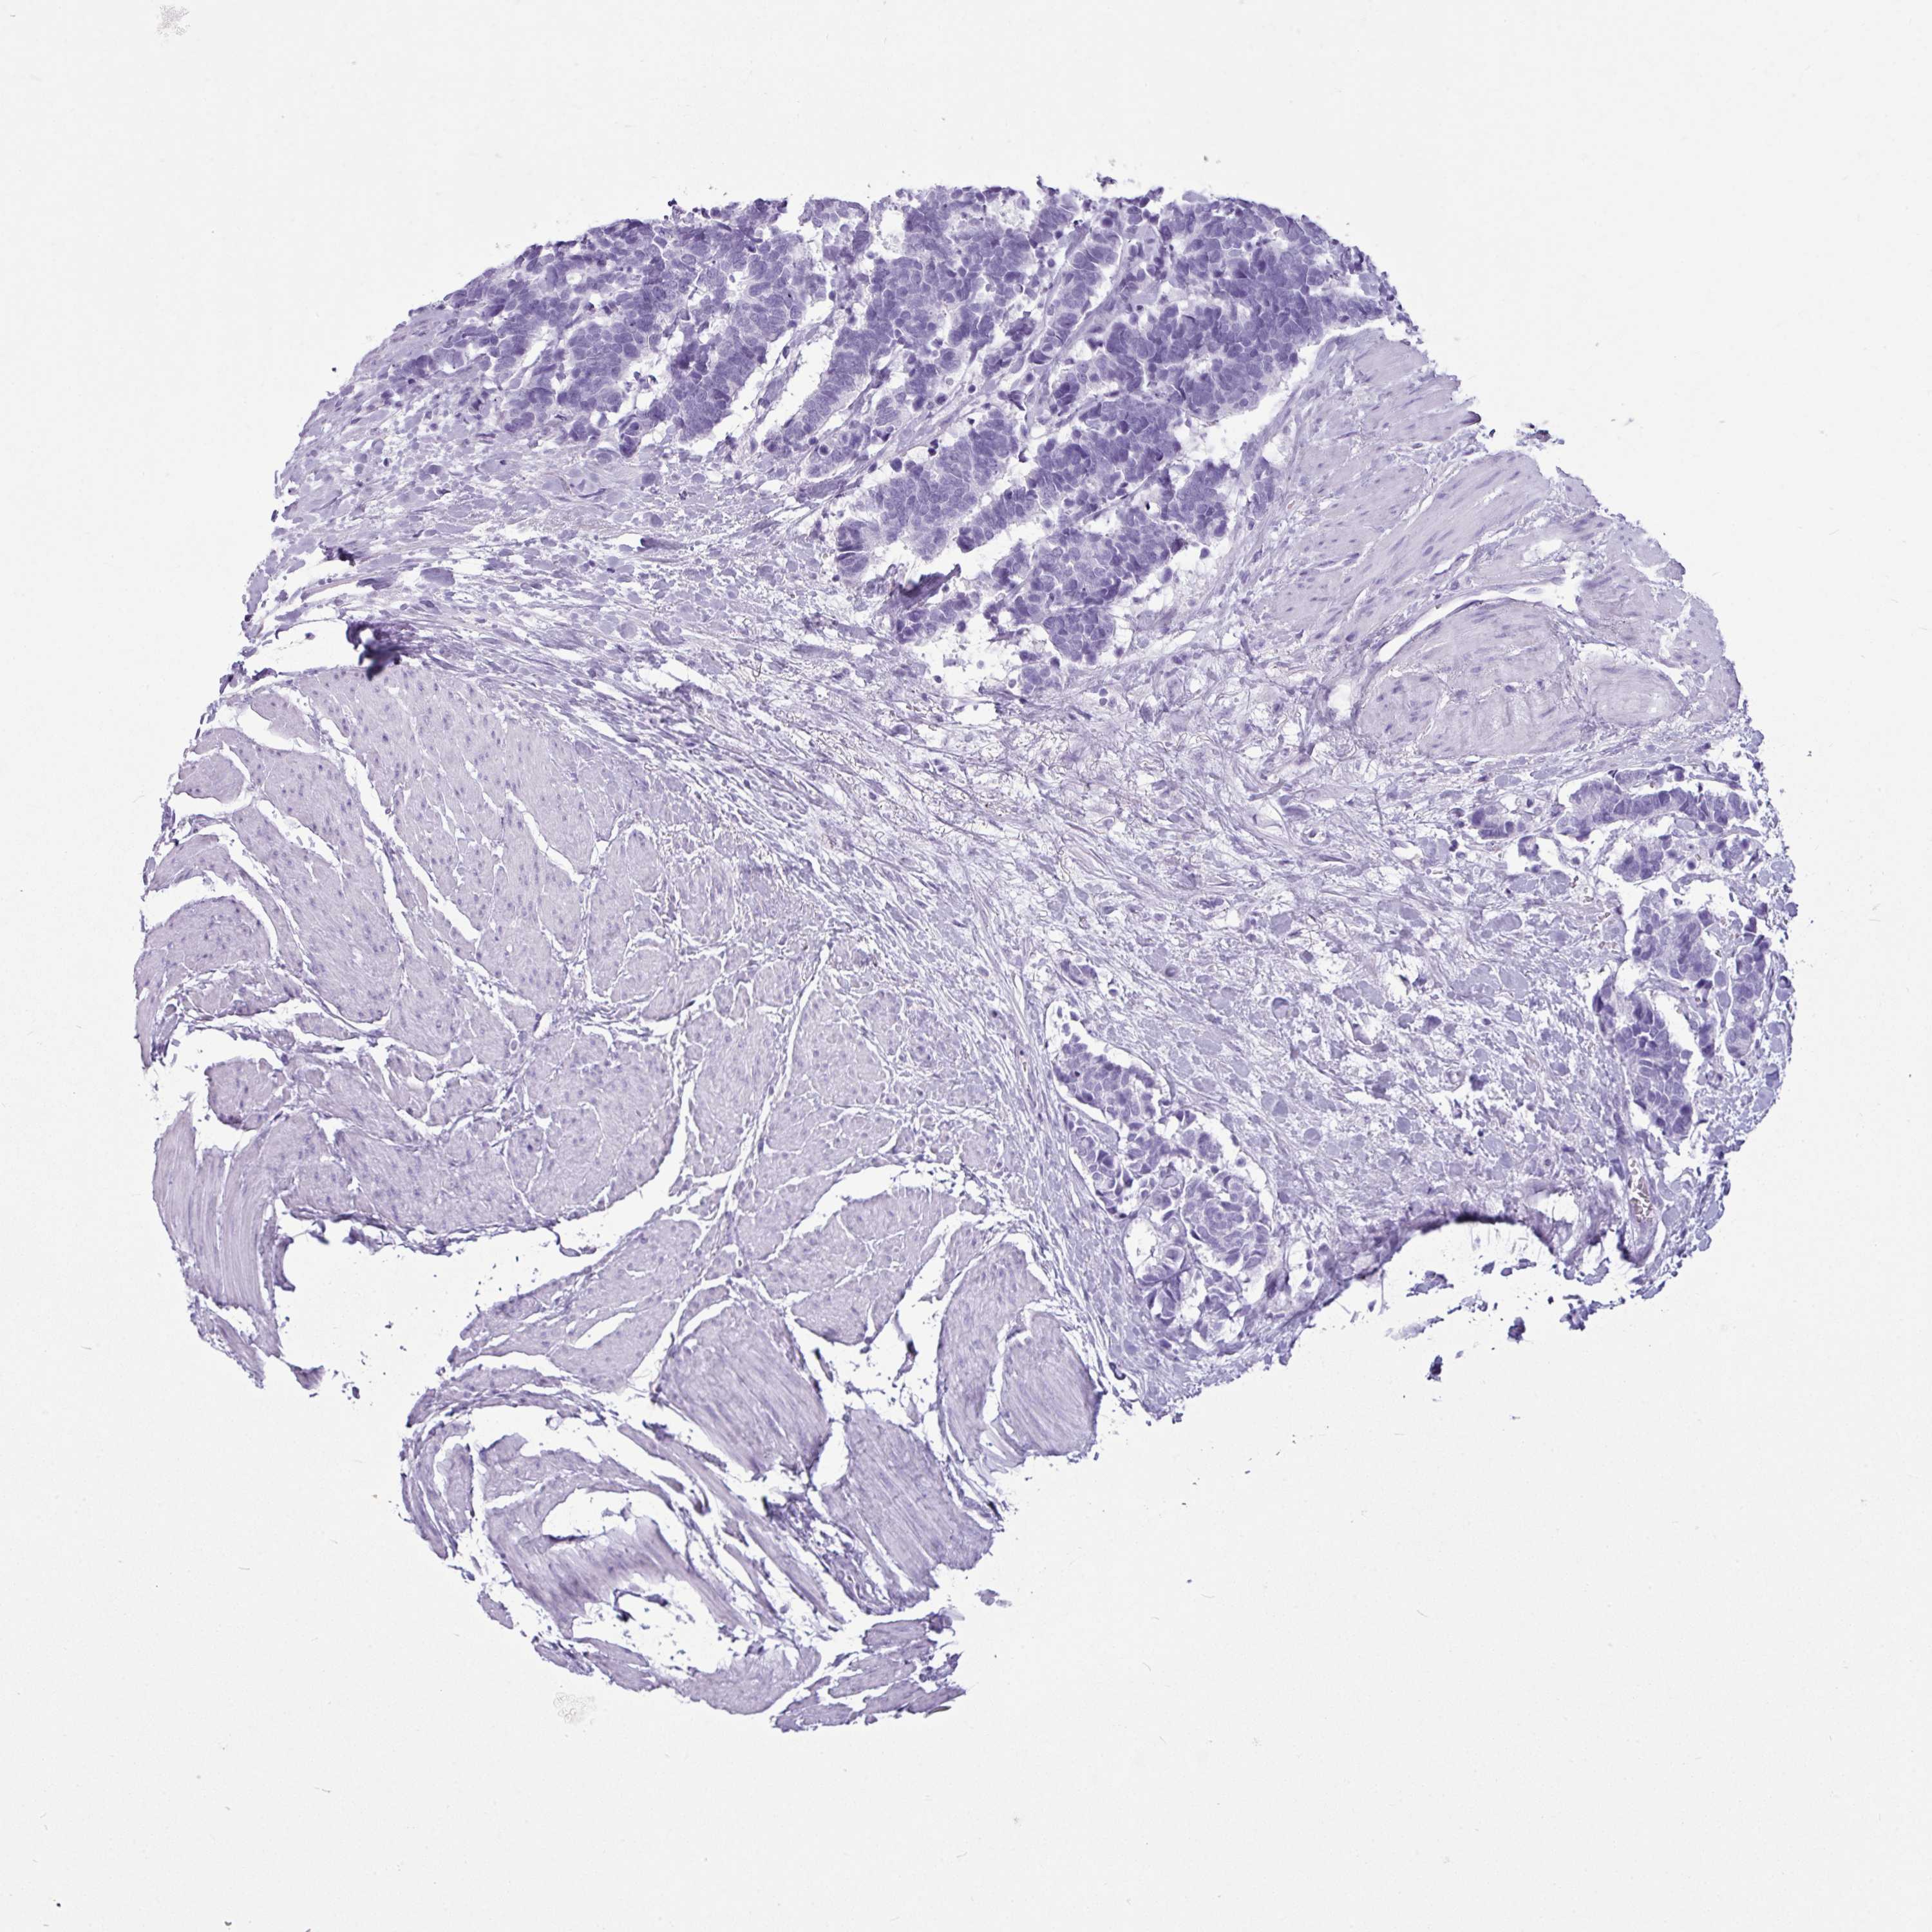

AMY1C